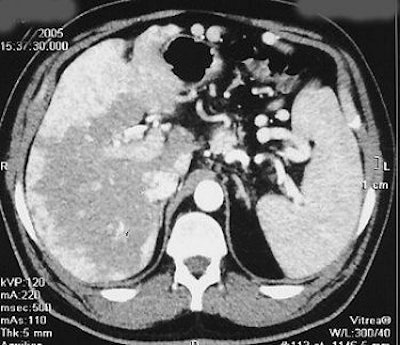

Same patient. Above, CT scan 12 weeks after the start of the radionuclide treatment. Below, CT scan done six weeks after completed therapy of 90Y DOTA TATE. RECIST = disease stability. Serum CgA increased. Patient was clinically well at six-month follow-up. Images courtesy of Dr. Jaroslaw Cwikla.